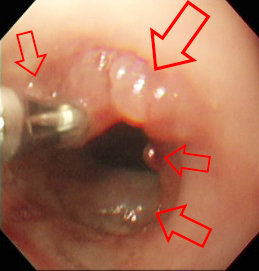

下の2枚の画像は、血便がずっと続いているとのことで内視鏡検査を行ったものです。

たくさんのポリープ(赤矢印)

が見られています。

生検鉗子で組織を採取し、病理検査を行ったところ、直腸ポリープと診断されました。

後日、プルスルーの術式にて当該の結腸、直腸を摘出しています。病理検査では、多発性炎症性ポリープ、慢性直腸炎という評価でした。現在、術後経過を観察中です。細いウンチ、下血、下痢などの症状は改善されてきています。